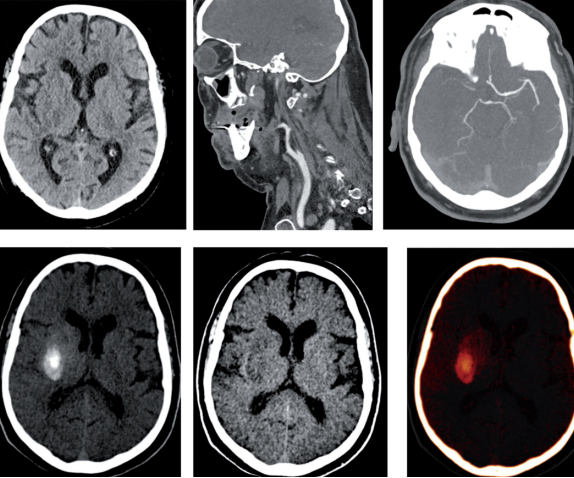

双能量CT有助于闭塞性颈动脉支架术后抗血小板方案选择